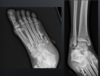

what type of fracture?

Pylon

Infications for foot ankle CT

Fx surgical planning Post op, healing comps or non unions tarsal soalitions cortical tumors gout

fx?

calc

45

talar fx

46

lisfranc